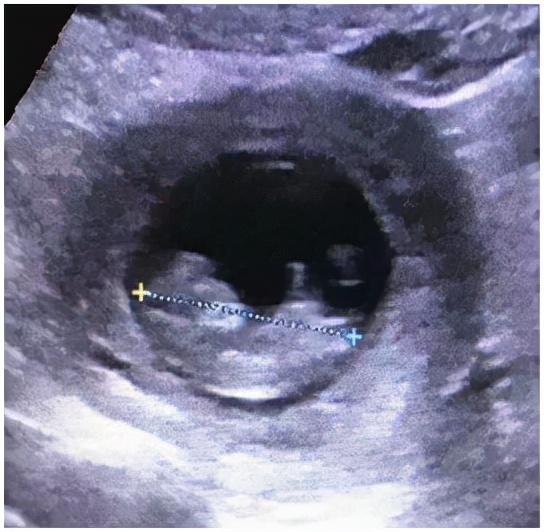

术后病理发现:左侧输卵管妊娠。113.b超复查:宫腔内见49*33*48孕囊,内见卵黄囊及胚芽,心管搏动,头臀长37mm,提示早孕。患者没有腹痛和阴道出血。11月17日,经过复查b超无异常,王女士终于露出了幸福的笑容,和家人一起幸福地出院了。